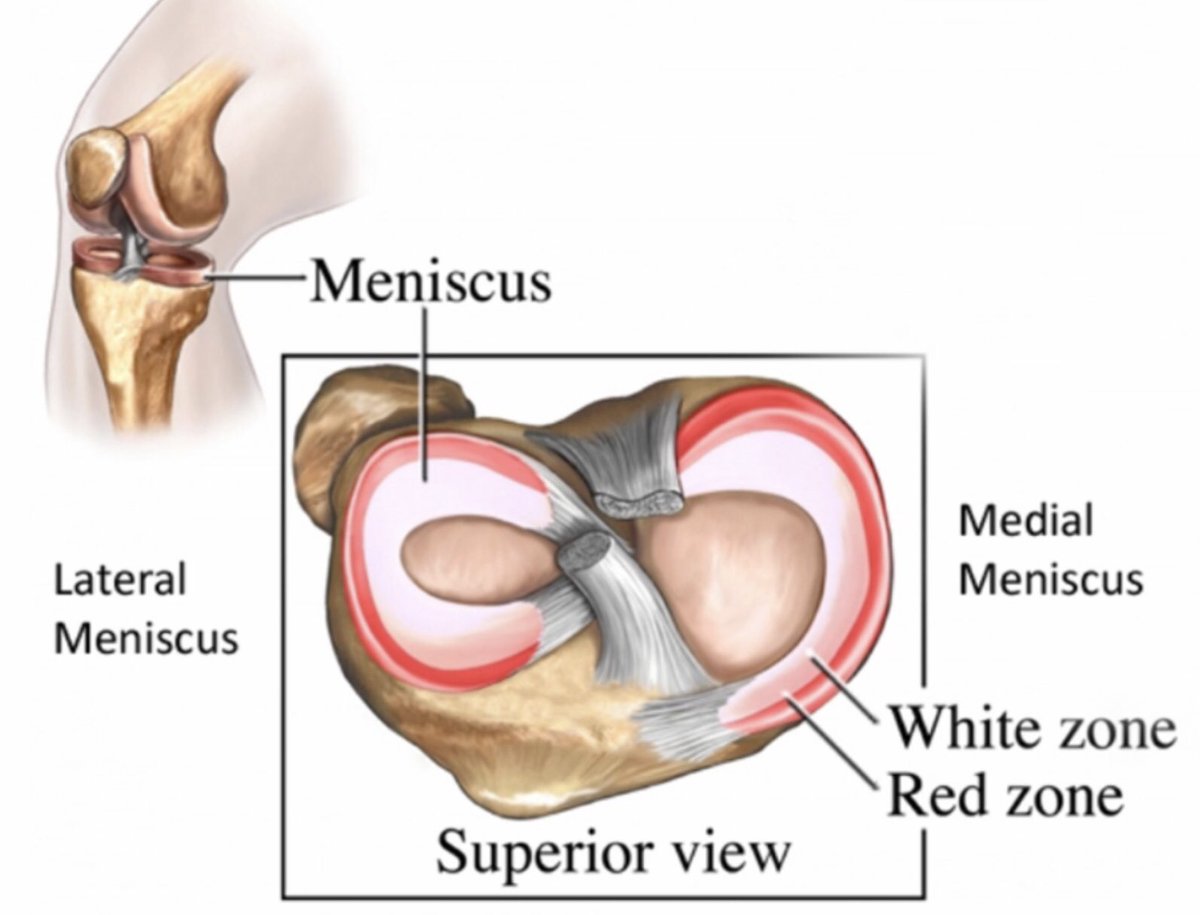

Анатомические изображения менисков и коленного сустава

Раздел: Иллюстрированные советы